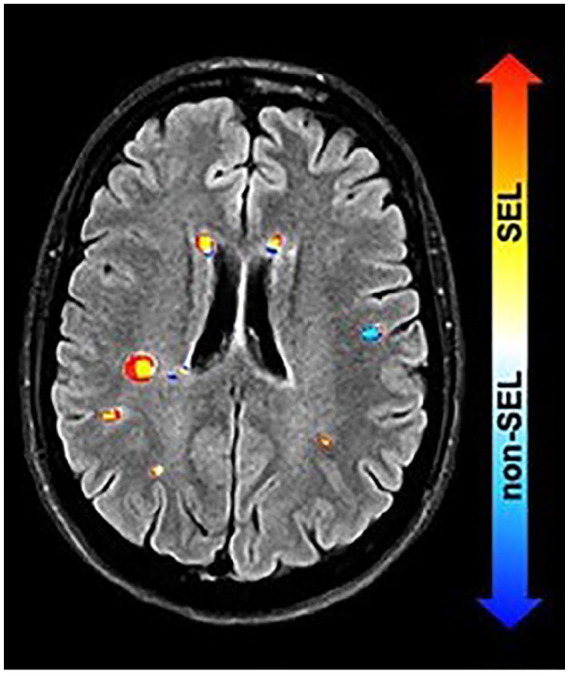

在多发性硬化症(MS)中,越来越多的残疾被认为是由于中枢神经系统(CNS)内持续的慢性炎症而发生的。这种情况被称为阴燃性神经炎症,存在于MS的临床谱中,目前被认为对现有的疾病改善疗法具有相对抗性。慢性活动性白质病变是阴燃性神经炎症的重要组成部分。最初以尸检标本为特征,使用先进的神经成像技术和后处理方法来可视化体内慢性活动性病变(CALs)的多种方法正在迅速出现。在这些与CALs相关的体内成像中,顺磁边缘病变(prl)是由富含铁的小胶质细胞和巨噬细胞形成的病灶周围边缘定义的,而缓慢扩张的病变是根据随时间的线性、同心扩张来识别的。近年来,一些纵向研究将体内检测到的CALs的发生与更具侵袭性的疾病病程联系起来。prl对多发性硬化症具有高度特异性,因此最近被纳入多发性硬化症的诊断标准。它们还具有作为生物标志物的预后潜力,可识别有早期和严重疾病进展风险的患者。这些进展可能会显著影响MS的护理和新疗法的评估。本文介绍了CAL生物学和影像学的最新知识,以及CAL与ms自然历史的相关性。此外,我们概述了当前和未来CAL体内生物标志物的考虑,强调了其评估的验证、标准化和自动化的必要性。

In multiple sclerosis (MS), increasing disability is considered to occur due to persistent, chronic inflammation trapped within the central nervous system (CNS). This condition, known as smoldering neuroinflammation, is present across the clinical spectrum of MS and is currently understood to be relatively resistant to treatment with existing disease-modifying therapies. Chronic active white matter lesions represent a key component of smoldering neuroinflammation. Initially characterized in autopsy specimens, multiple approaches to visualize chronic active lesions (CALs) in vivo using advanced neuroimaging techniques and postprocessing methods are rapidly emerging. Among these in vivo imaging correlates of CALs, paramagnetic rim lesions (PRLs) are defined by the presence of a perilesional rim formed by iron-laden microglia and macrophages, whereas slowly expanding lesions are identified based on linear, concentric lesion expansion over time. In recent years, several longitudinal studies have linked the occurrence of in vivo detected CALs to a more aggressive disease course. PRLs are highly specific to MS and therefore have recently been incorporated into the MS diagnostic criteria. They also have prognostic potential as biomarkers to identify patients at risk of early and severe disease progression. These developments could significantly affect MS care and the evaluation of new treatments. This review describes the latest knowledge on CAL biology and imaging and the relevance of CALs to the natural history of MS. In addition, we outline considerations for current and future in vivo biomarkers of CALs, emphasizing the need for validation, standardization, and automation in their assessment.